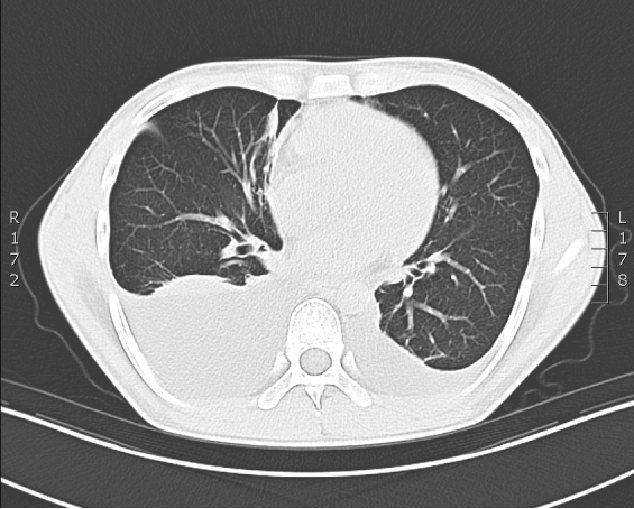

• 胸部CT平扫:胸廓对称,气管纵隔居中。双肺支气管血管束增多、模糊,双肺散在少许条片影。纵隔内未见明显肿大淋巴结影,心脏不大,心包见少许积液。双侧胸膜无增厚,双侧胸腔见较多积液。腹腔可见积液

印象:1、双侧胸腔积液伴双肺下叶膨胀不全,双肺少量不张;心包少量积液;腹腔积液,建议进一步检查